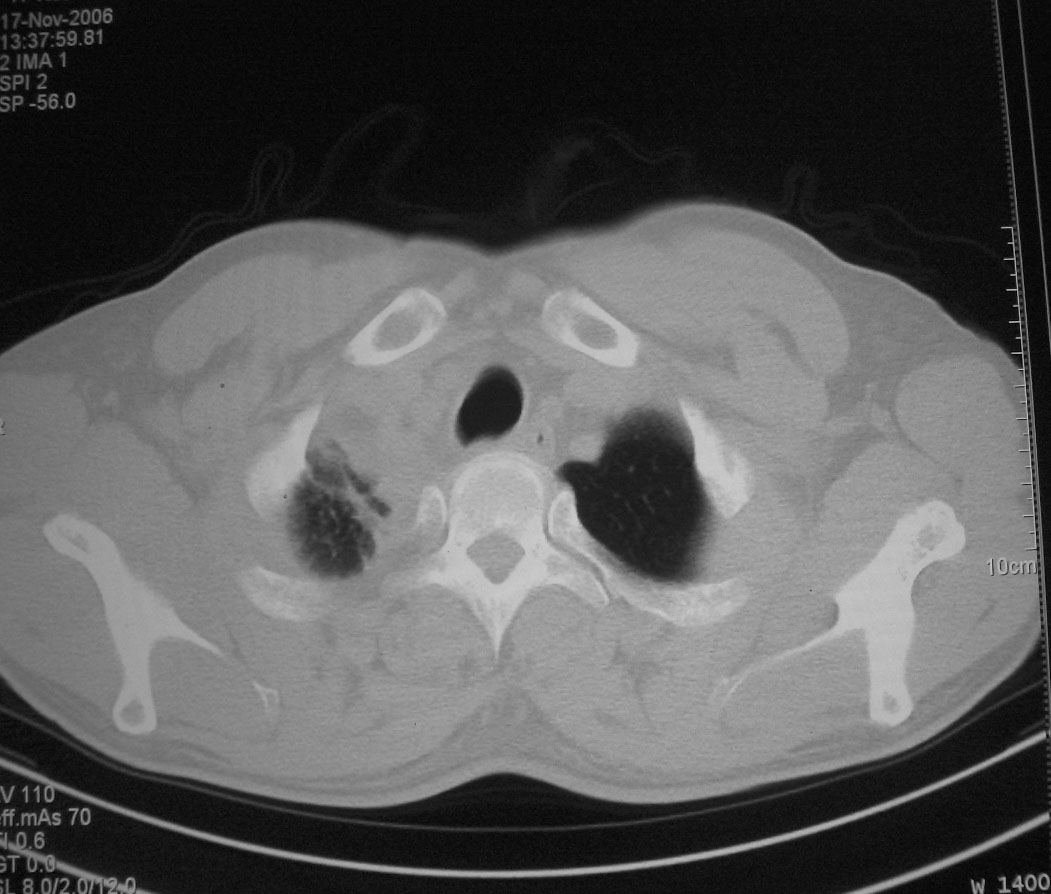

标题: CT5485:[原创]肺部占位请讨论

右肺上叶中央型肺癌并上叶肺不张、纵隔淋巴结肿大

右上叶支气管后壁明显增厚,支持右肺上叶中央型肺癌伴右上叶肺不张、纵隔淋巴结肿大。

右上叶支气管后壁明显增厚,支持右肺上叶中央型肺癌伴右上叶肺不张、纵隔淋巴结肿大。建议支气管镜检查。

右上叶支气管开口变窄,纵隔见肿大的淋巴结。支持右上叶中心型肺癌并右上叶不张纵隔淋巴结肿大。

右肺上叶中央型肺癌并上叶肺不张、纵隔淋巴结肿大.右侧少量胸腔积液。

右肺上叶支气管后壁增厚,呈鼠尾状狭窄,纵隔内未见明显增大的淋巴结影,考虑为中央型肺癌伴右上肺不张